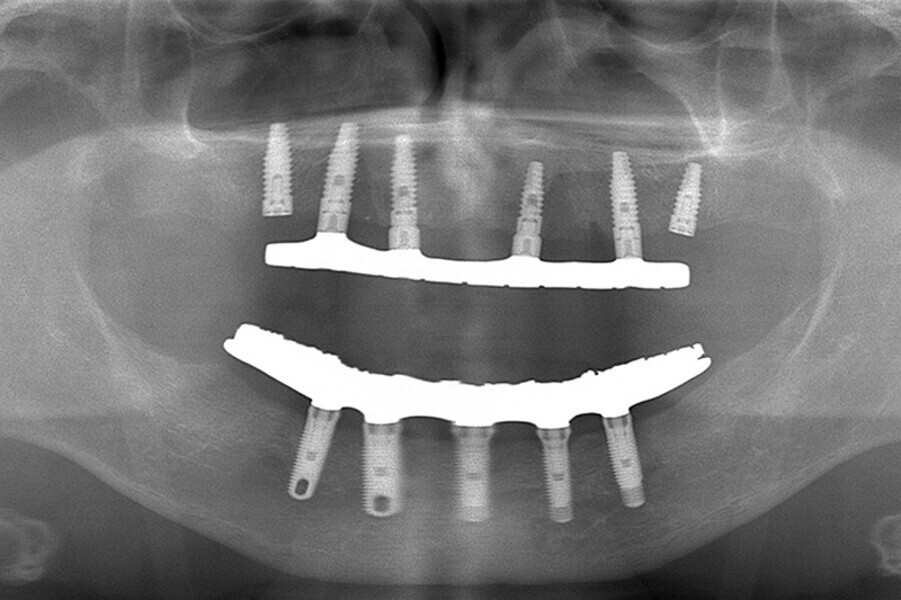

Fig. 7. Rx Pre-operatoria, Prótesis híbrida inmediata con 10 años de evolución y Rx Control a los 10 años.

Fig. 8. Rx Pre-operatoria, Prótesis híbrida inmediata con 10 años de evolución y Rx Control a los 10 años.